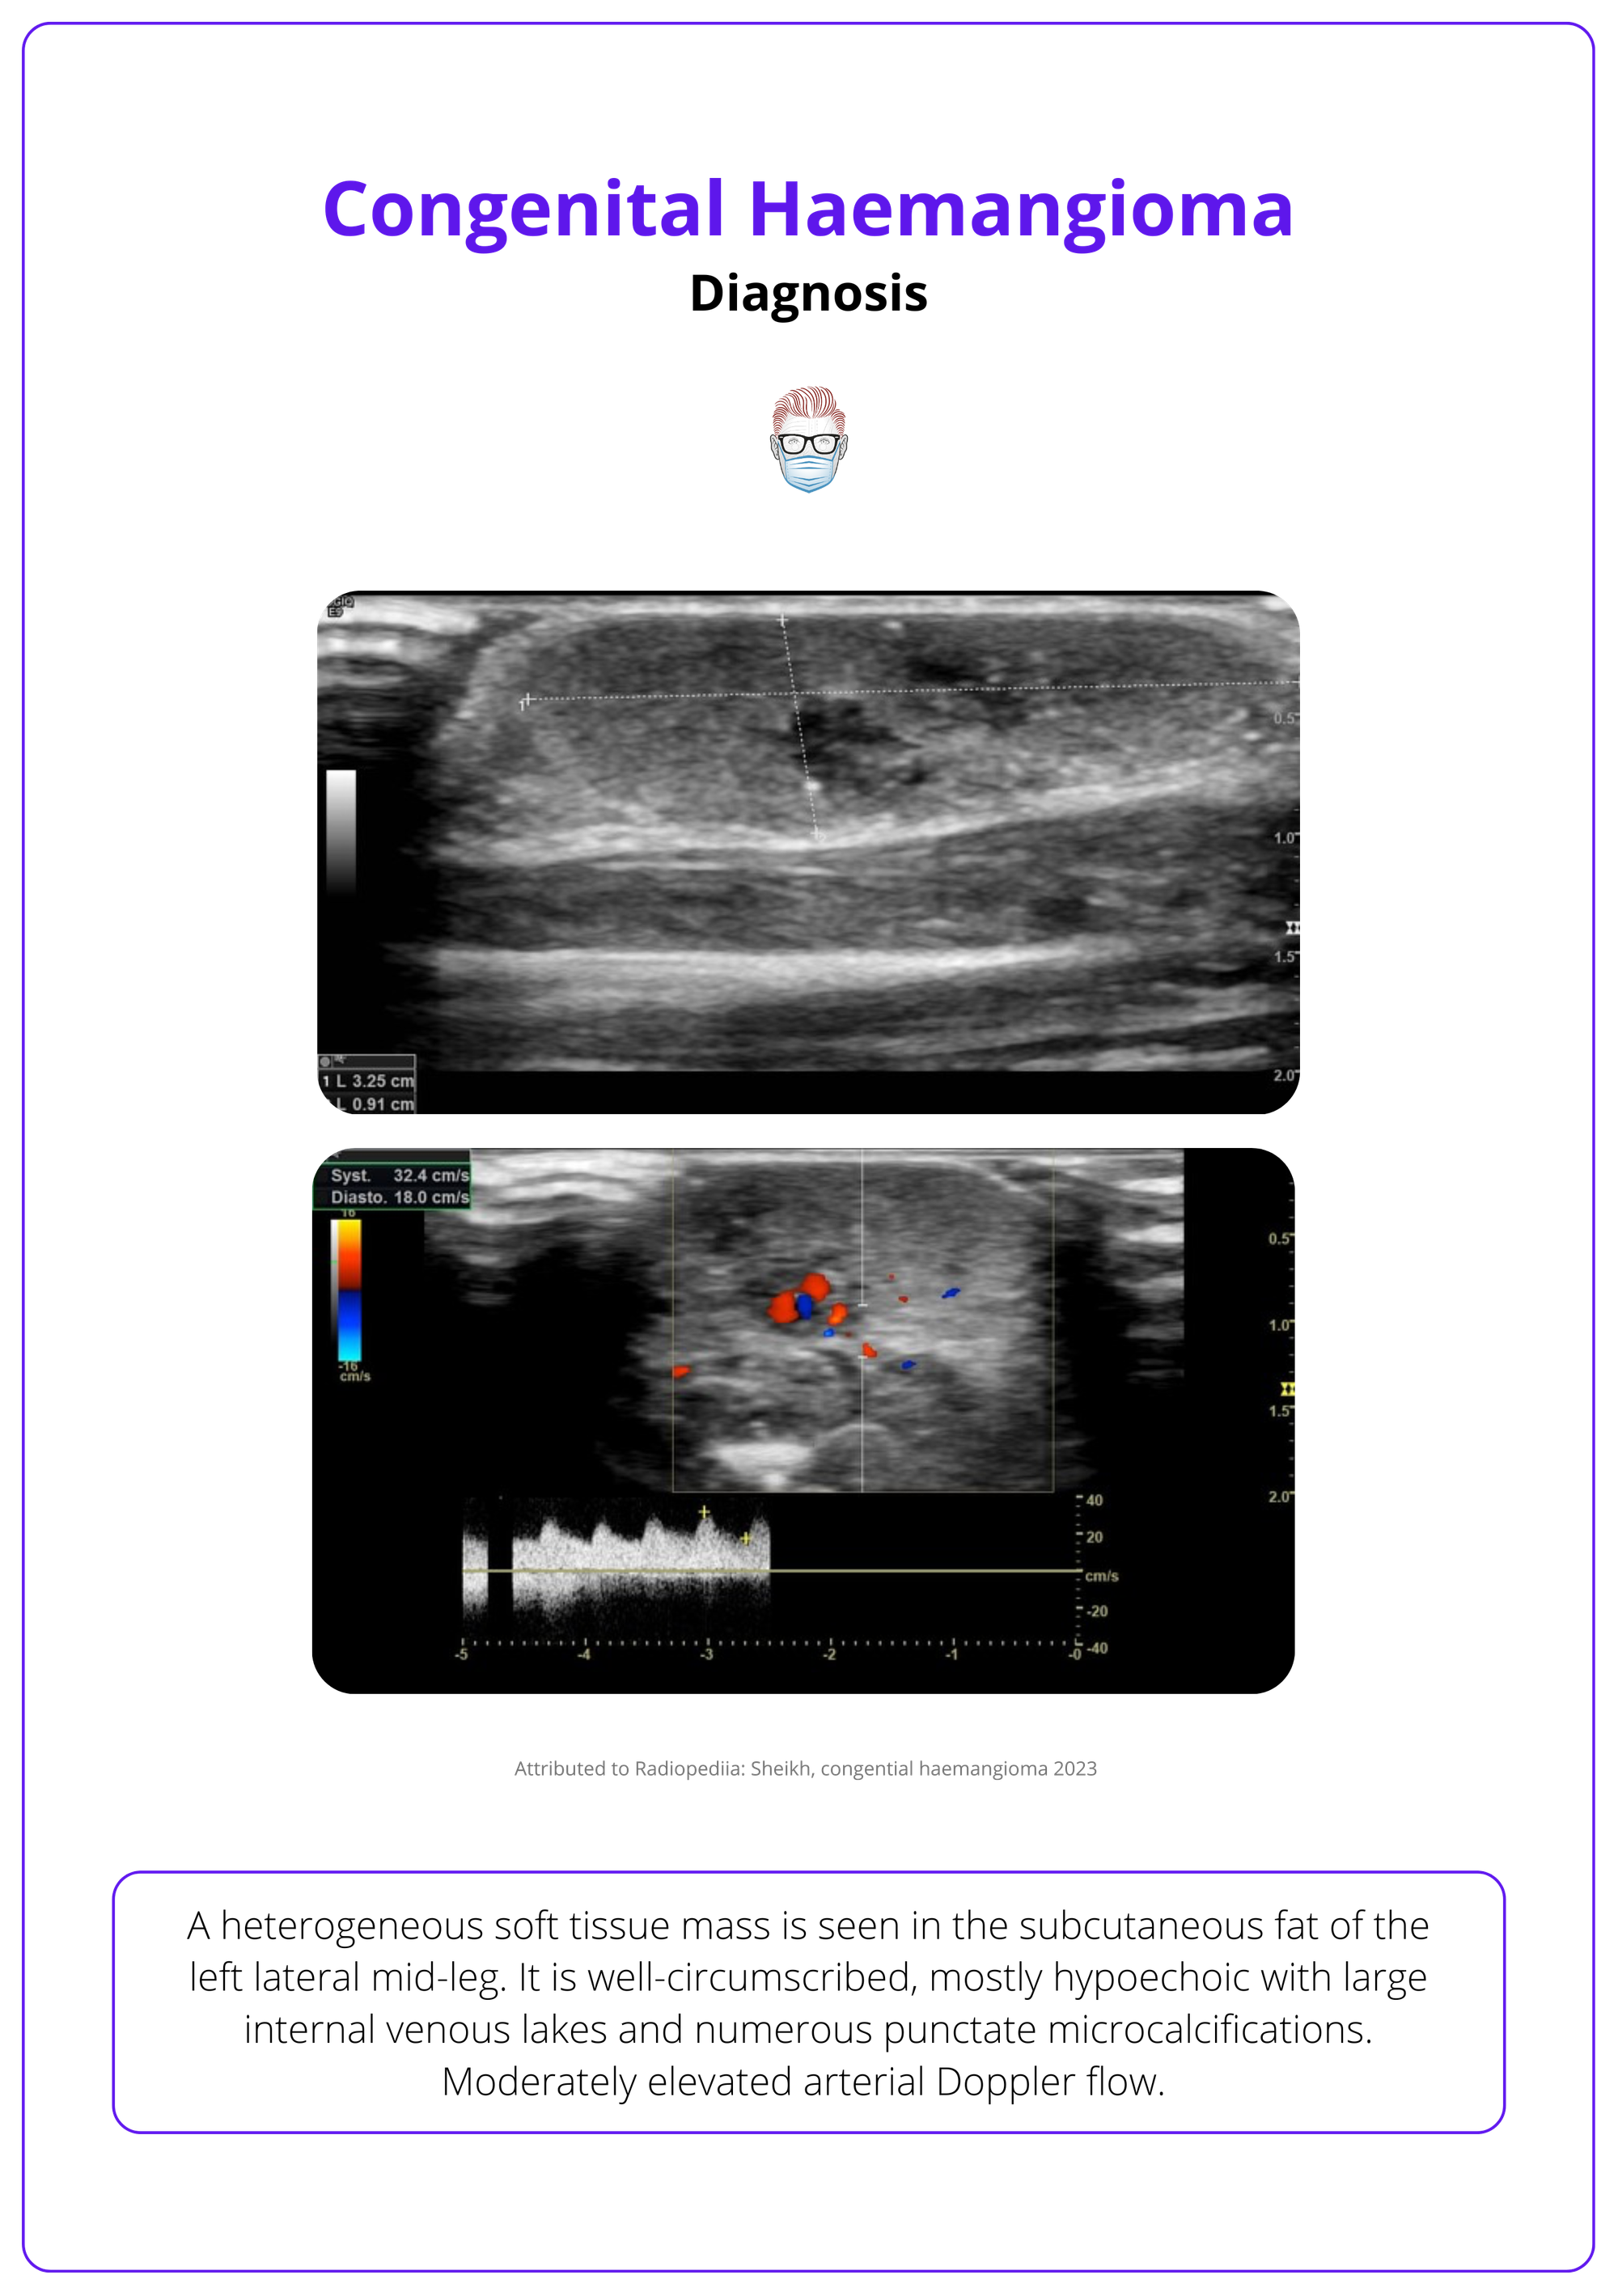

CHs are well-circumscribed, highly vascularised tumours with enlarged arteries and veins, and high-velocity flow (Nasseri, 2014).

- Hypoechoic, homogeneous, or heterogeneous.

- Calcifications may appear (seen in 2 RICHs and 1 PICH).

- Microshunts are more frequent in NICH.

An ultrasound of a congenital haemangioma is illustrated below.